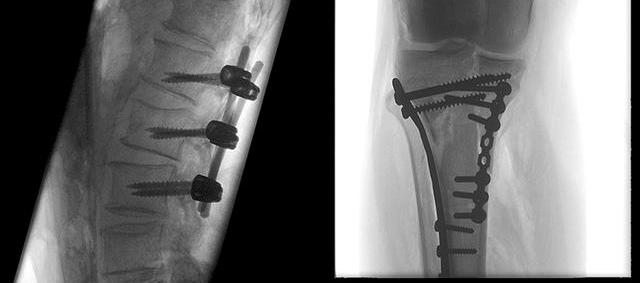

C型臂X射线机,是指机架为C型的X线摄影设备,用于手术中的实时动态成像。C型臂具有辐射剂量小、感染风险低、占地面积小、便于移动等优势,现广泛应用于医院骨科、外科、妇科等科室。C型臂主要用途包括骨科打钉、整骨、复位;外科植入起搏器、取体内的异物、部分造影术、部分介入手术;以及配合臭氧机治疗疼痛、小针刀治疗、妇科输卵管导引手术等。

旗下的PLX7200型移动式三维C型臂等产品在市场获得了良好口碑,能够提供术中3D成像,适用于骨科、外科、矫形外科、泌尿外科、脊柱外科、腹部外科、疼痛科、消化科、妇科及手术室等,大幅度拓宽骨科手术范围,提高诊治水准。支持骨组织活检、脊柱椎弓根螺钉植入术、长管状骨髓内钉固定术、及适合采用螺钉固定的手、足骨折手术等骨科、创伤科复杂诊治。